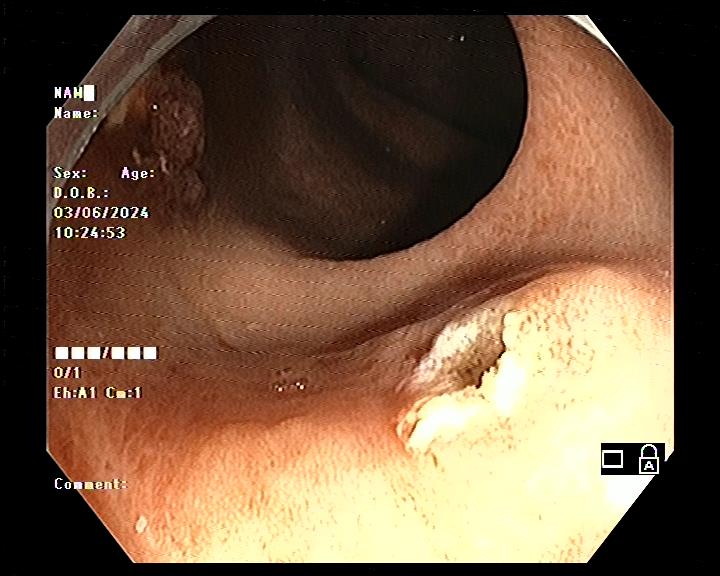

Làm gì khi phát hiện có polyp trong đại tràng? Khi phát hiện polyp đại tràng, bác sĩ có thể cắt bỏ nó và làm xét nghiệm tìm xem có tế bào ung thư hay không. Hầu hết các polyp được loại bỏ trong quá trình nội soi đại tràng.

Biến chứng có thể xảy ra khi cắt polyp đại tràng: cắt polyp đại tràng là phương pháp an toàn, rất hiếm khi xuất hiện biến chứng. Biến chứng có thể xảy ra nhưng không phổ biến bao gồm: chảy máu từ vị trí cắt và thủng đại tràng với tỉ lệ 0,1%. Chảy máu từ chỗ cắt polyp đại tràng có thể gặp ngay trong lúc cắt hoặc vài ngày sau nhưng hiện nay có nhiều thiết bị hỗ trợ cầm máu ngay trong quá trình cắt polyp. Thủng đại tràng thường cần phải phẫu thuật.